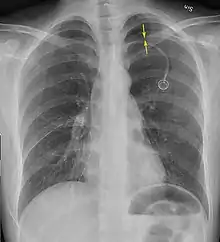

| A large right-sided spontaneous pneumothorax (left in the image). An arrow indicates the edge of the collapsed lung | |

Chest X-ray

A plain chest radiograph, ideally with the X-ray beams being projected from the back (posteroanterior, or "PA"), and during maximal inspiration (holding one's breath), is the most appropriate first investigation.[25] It is not believed that routinely taking images during expiration would confer any benefit.[26] Still, they may be useful in the detection of a pneumothorax when clinical suspicion is high but yet an inspiratory radiograph appears normal.[27] Also, if the PA X-ray does not show a pneumothorax but there is a strong suspicion of one, lateral X-rays (with beams projecting from the side) may be performed, but this is not routine practice.[14][18]

It is not unusual for the mediastinum (the structure between the lungs that contains the heart, great blood vessels and large airways) to be shifted away from the affected lung due to the pressure differences. This is not equivalent to a tension pneumothorax, which is determined mainly by the constellation of symptoms, hypoxia, and shock.[13]

The size of the pneumothorax (i.e. the volume of air in the pleural space) can be determined with reasonable accuracy by measuring the distance between the chest wall and the lung. This is relevant to treatment, as smaller pneumothoraces may be managed differently. An air rim of 2 cm means that the pneumothorax occupies about 50% of the hemithorax.[14] British professional guidelines have traditionally stated that the measurement should be performed at the level of the hilum (where blood vessels and airways enter the lung) with 2 cm as the cutoff,[14] while American guidelines state that the measurement should be done at the apex (top) of the lung with 3 cm differentiating between a "small" and a "large" pneumothorax.[28] The latter method may overestimate the size of a pneumothorax if it is located mainly at the apex, which is a common occurrence.[14] The various methods correlate poorly, but are the best easily available ways of estimating pneumothorax size.[14][18] CT scanning (see below) can provide a more accurate determination of the size of the pneumothorax, but its routine use in this setting is not recommended.[28]

Not all pneumothoraces are uniform; some only form a pocket of air in a particular place in the chest.[14] Small amounts of fluid may be noted on the chest X-ray (hydropneumothorax); this may be blood (hemopneumothorax).[13] In some cases, the only significant abnormality may be the "deep sulcus sign", in which the normally small space between the chest wall and the diaphragm appears enlarged due to the abnormal presence of fluid.[15]

Anteroposterior inspired X-ray, showing subtle left-sided pneumothorax caused by port insertion